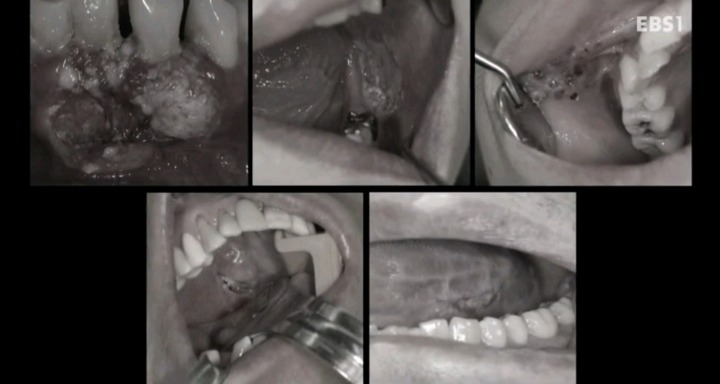

구강암 환자들은 혀를 잘라야한다는 사실에 큰 심리적 충격을 받는다.jpg

김순애 환자는 아직 다른 곳으로 전이가 되지않은 초기 설암이기 때문에 수술 후 혀를 복원하면 예후가 좋을 것이다.

ebs 명의- 구강암